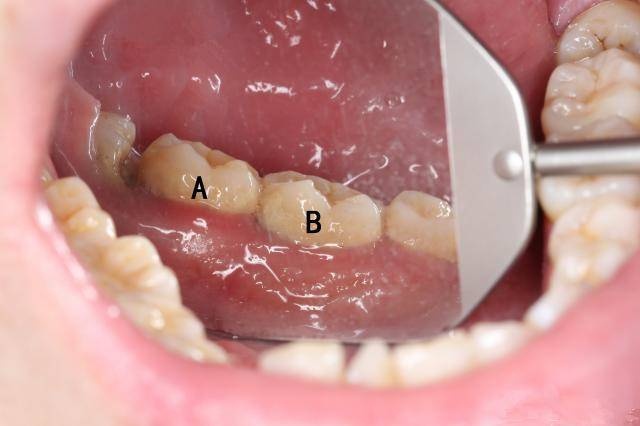

从不洗牙的人牙齿掉的快,为什么这么说呢?举个例子就知道啦!下图标注的A、B两颗牙齿表面看上去都没什么特别严重的问题。

但是其中脱落的B牙却是这样的:

估计很多人都觉得不可思议,这两颗牙看着都没那么脏啊?看着不脏,龈下却已经积满牙结石。